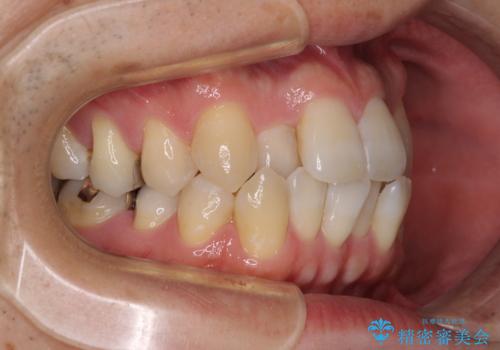

前歯のクロスバイト 目立たないワイヤー装置で矯正治療

- 前歯のクロスバイトを改善したいとのことで来院された患者様です。

マウスピース矯正では前歯の神経への負担が大きいことを懸念され、ワイヤー装置による矯正治療を行うこととしました。

舌の突出癖が認められたため、デコボコ改善に伴い前歯が前突する可能性があったため、舌のトレーニングをしっかりと行うよう指導しながら治療を進めることとしました。